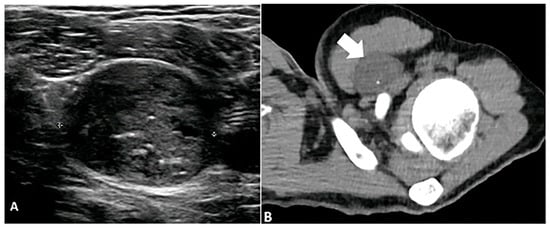

5.3. Pilomatricoma

- Le, C.; Bedocs, P.M. Calcifying Epithelioma of Malherbe; StatPearls Publishing: Treasure Island, FL, USA, 2018. [Google Scholar]

- Sunanda, D.P.; Rajashekhar, R.P.; Tanmay, C.; Gundappa, M. Pilomatricoma: A Case Report. Cureus 2024, 16, e63574. [Google Scholar]

- Li, L.; Xu, J.; Wang, S.; Yang, J. Ultra-High-Frequency ultrasound in the evaluation of paediatric pilomatricoma based on the histopathologic classification. Front. Med. 2021, 8, 673861. [Google Scholar]